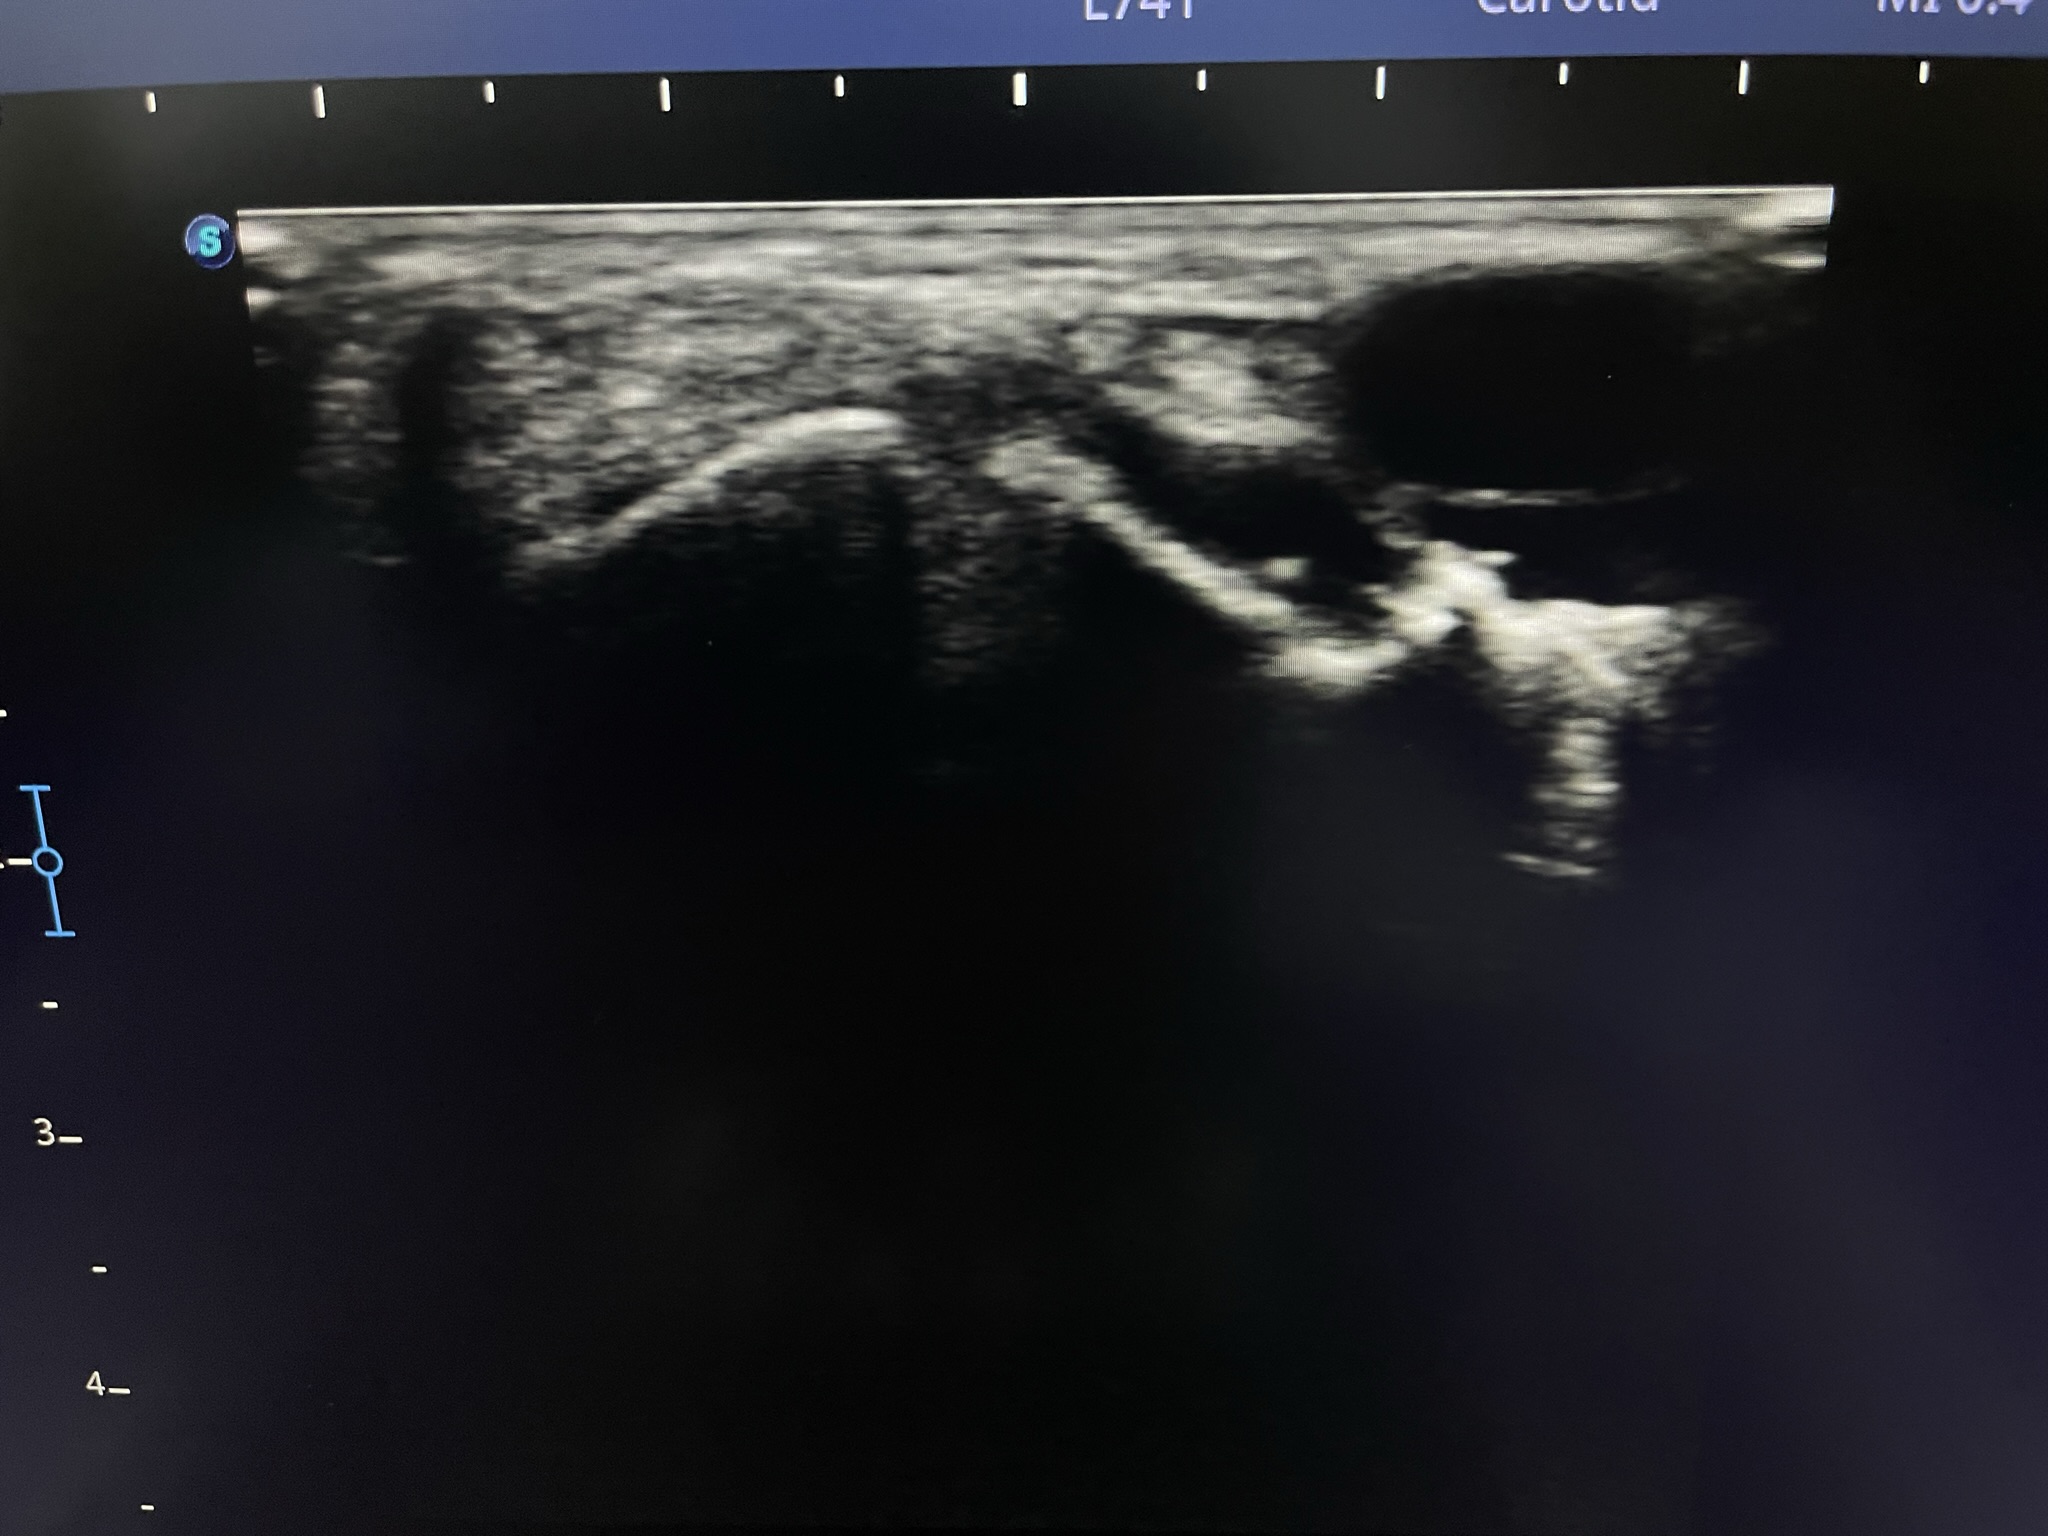

Клинический случай: тыльная гигрома запястья

Пациент с тыльной гигромой, подтверждённой на УЗИ. Выполнено хирургическое лечение, документированы этапы контроля и результаты.